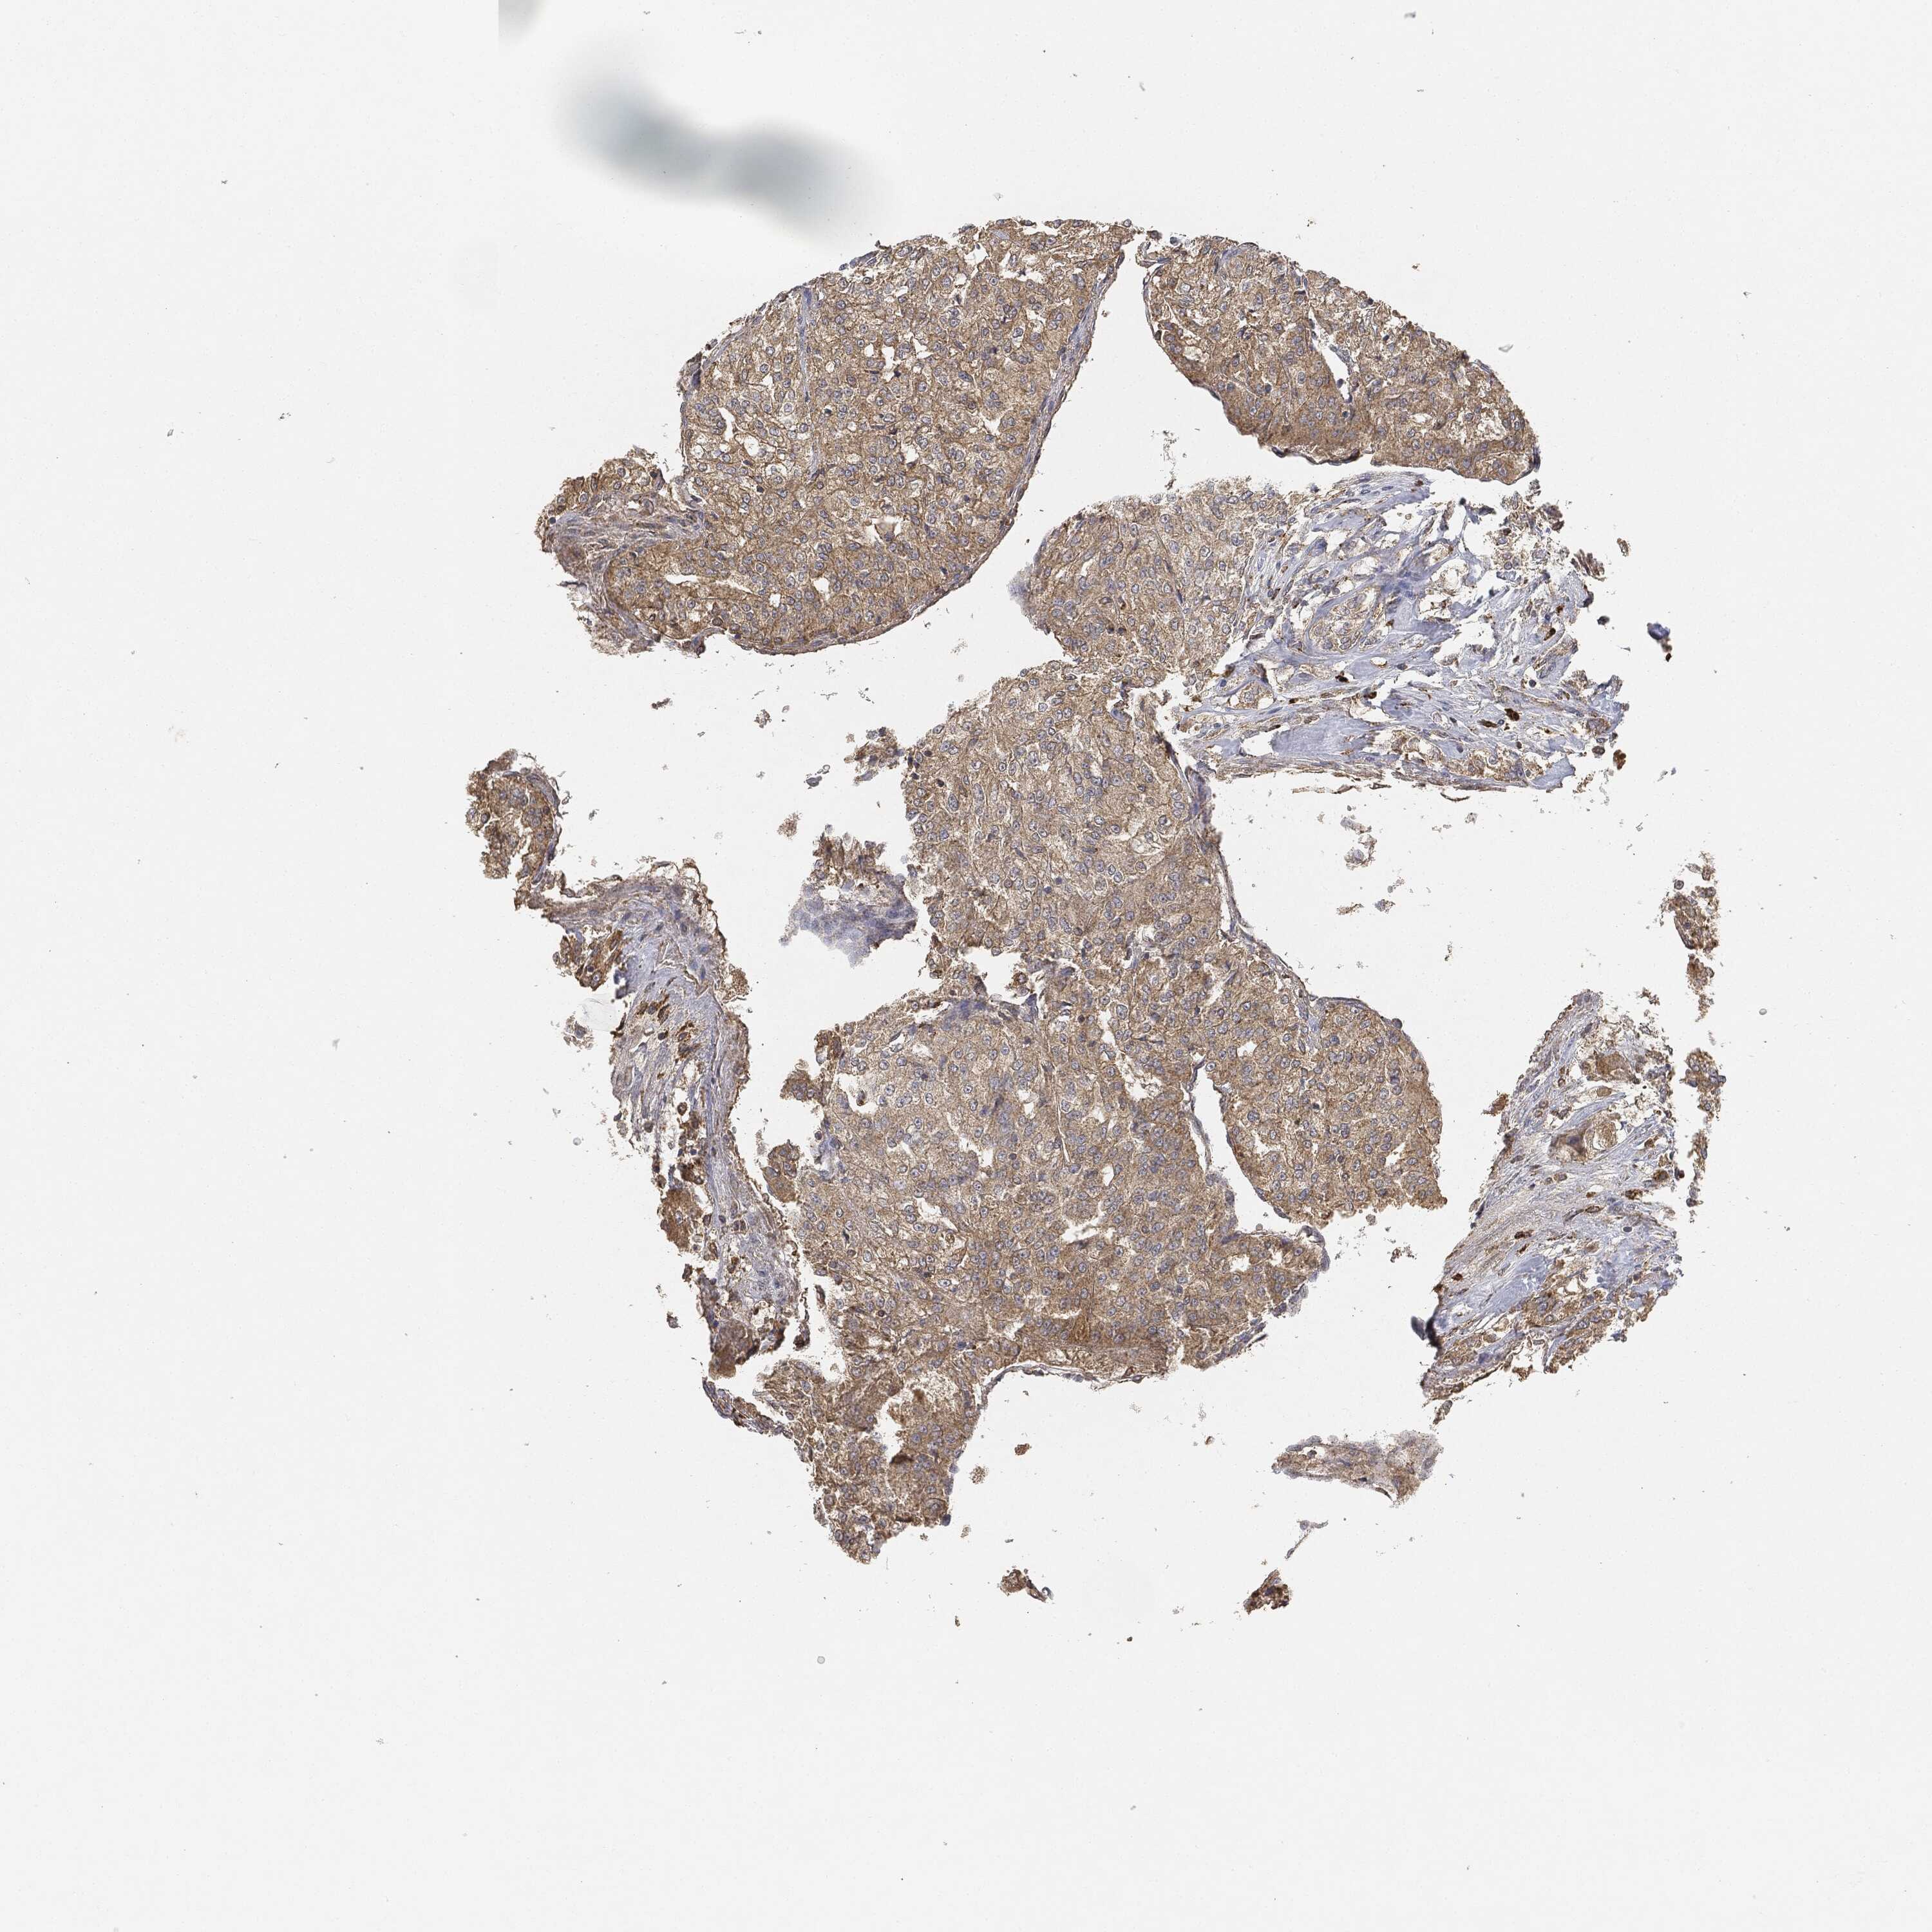

KIDNEY RENAL CLEAR CELL CARCINOMA (VALIDATION) - Interactive survival scatter ploti

EGFR is not prognostic in Kidney Renal Clear Cell Carcinoma (validation)

: 44.55

Average pTPM 89.3

Number of samples 100